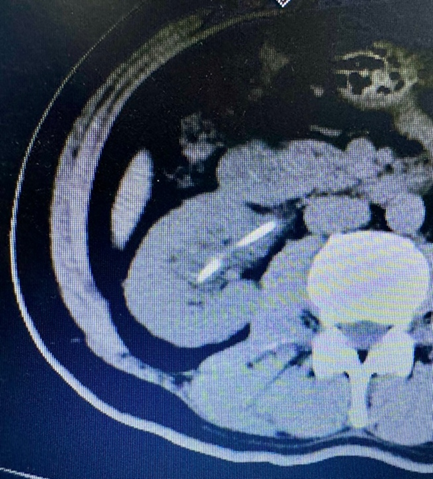

术后CT复查